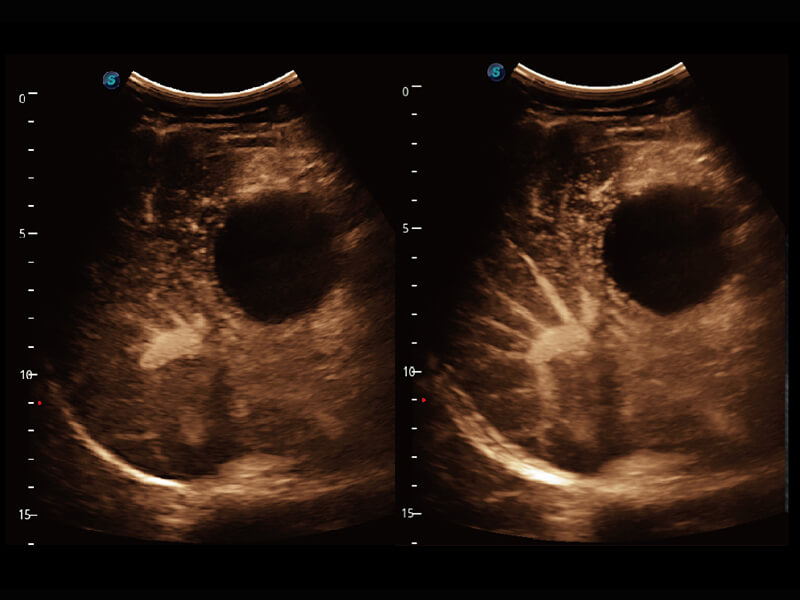

性能优异的硬件架构,极大提升超声系统的运行效率和数据处理能力。相比以往超声成像系统,Wis+平台为您带来极快的响应速度和成像帧频,提升检查流畅度。

S60探头工艺,从前端信号处理每一个环节采集无损声学数据,真实还原组织原貌,再现解剖细节。